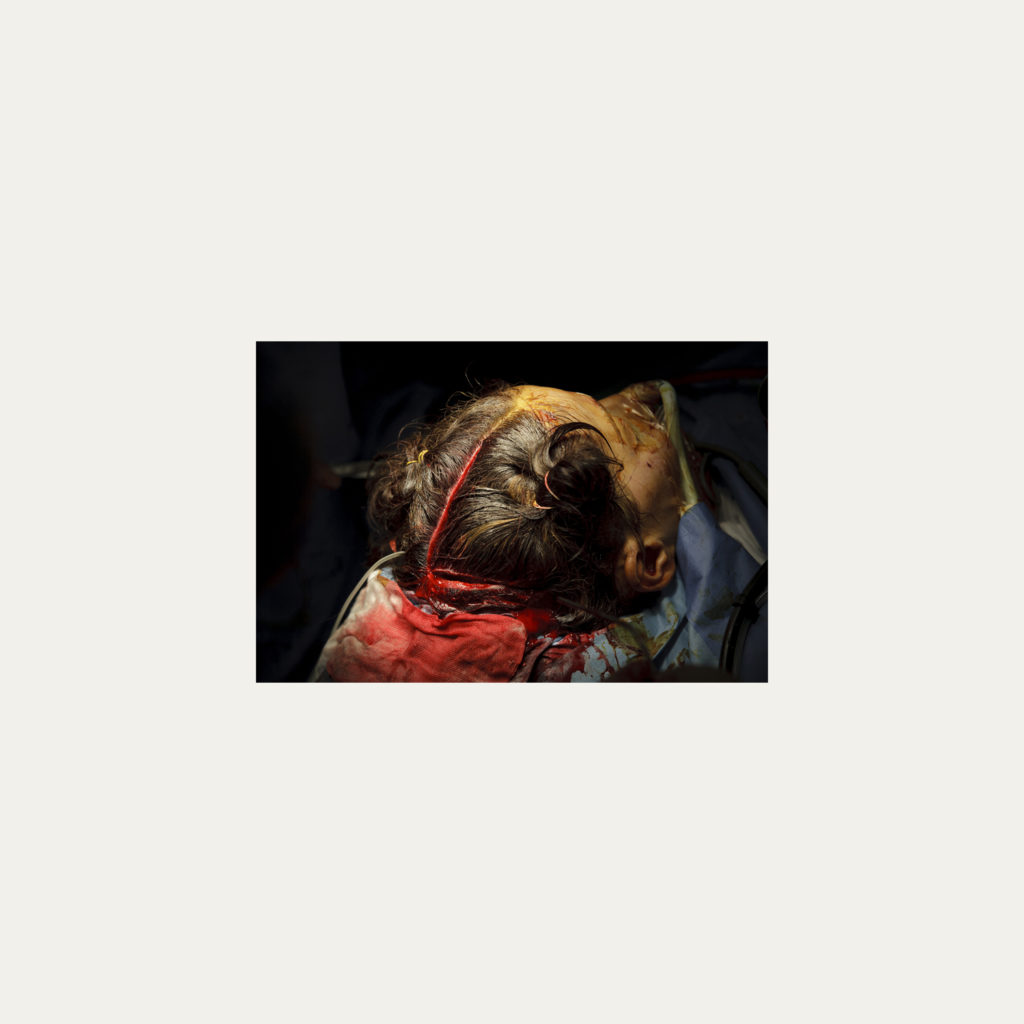

« Nature Morte » est la recherche de l’instant, pendant une intervention chirurgicale où la tête du patient opéré se retrouve seule dans le champ photographié. Aucune main intervenant, peu d’instruments chirurgicaux visibles, laissent le fragment de corps opéré existé pour lui-même. Les têtes, ainsi isolées, en deviennent presque des objets.

Cette approche est intensifiée par la présentation : dans de grands cadres carrés et passe-partout blancs, les photos de petit format font référence aux papillons épinglés de la collection d’un entomologiste.

Face à ces images, une forme de recueillement est nécessaire, s’approcher doucement pour s’approprier tous les détails des images.

Le caractère éminemment esthétique est souligné/donné par les gammes de couleur, la lumière précise sur la tête photographiée, les brillances partielles, renforçant également l’aspect pictural, les textures réelles.

L’humain présent dans ces images est celui qui rompt avec l’invisible et donne à voir l’architecture même de sa chair.